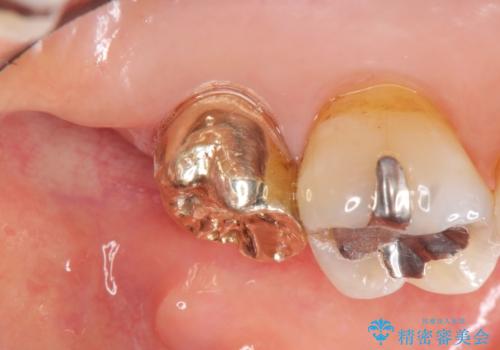

クラウンの将来的な虫歯の再発を防ぐために周囲の歯ぐきを切除することで歯の高さを出し安定した歯周環境にしたのち噛み心地の良いゴールドクラウンを製作します。

クラウンを装着した歯の虫歯の再発を防ぎ長い予後を期待するために削った箇所をしっかりとかぶせる適合の良さが必要はもちろんですが、セメントの漏洩を防ぐためにクラウンの十分な支台高径を歯周外科を行い獲得しました。